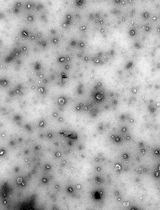

Oral administration of colon-targeting nanoformulations holds many advantages over the systemic delivery of free drugs, or traditional nontargeting formulations in the treatment of ulcerative colitis (UC). Currently, the most conventional method for constructing colon-targeting drug delivery systems (DDS) is by integrating the biocompatible materials poly(lactic-co-glycolic acid) (PLGA) and polylactic acid (PLA) into a copolymer. This PLGA/PLA-polyethylene glycol-folic acid (PEG-FA) copolymeric nanoformulation effectively delivers the drugs for uptake by various human colon cancer cells (e.g., HT-29 and HCT-116) and mouse colon cancer cells (CT-26). There is, however, a distinct lack of comprehensive protocols for the construction of such copolymer. This protocol details an easy-to-follow single-step method for the construction of a colon-targeting PLGA/PLA-PEG-FA nanoformulation, which encapsulates a fluorescent dye and demonstrates the visualization of its cell uptake in vitro.

Compared with other nanomaterials, FDA-approved poly(lactic-co-glycolic acid) (PLGA), polylactic acid (PLA), and Polycaprolactone (PCL) polymers are low-toxic, biodegradable, and can load both hydrophobic and hydrophilic drugs (Sindeeva et al., 2021). These materials have also proven easy to co-polymerize and form complex nanoparticles. Recently, many laboratories, ours included, have shown that PLGA/PLA copolymer composed nanoparticles are colon-targeting and biocompatible (Zhao et al., 2013; Zhang et al., 2018). Additionally, we co-polymerized PLGA nanoparticles with PLA-polyethylene glycol-folic acid (PEG-FA) (a PLA-PEG polymer with folic acid modification), enhancing the targeting ability towards folic acid receptors on intestinal epithelial cells. Subsequent reassembling of PLGA/PLA-PEG-FA nanoparticles into a hydrogel further improves their colon-targeting efficiency (Zhang et al., 2018). In this protocol, we will demonstrate the use of PLGA and PLA-PEG-FA as starting materials to make PLGA/PLA-PEG-FA copolymer nanoparticles. The uptake of these nanoparticles into epithelial cells would then be visualized by the incorporation of the fluorescent dye, Dil (dioctadecyl-tetramethylindocarbocyanine perchlorate). The nanoparticles prepared in this protocol have demonstrated their effectiveness in treating UC in recent research (Zhang et al., 2018).